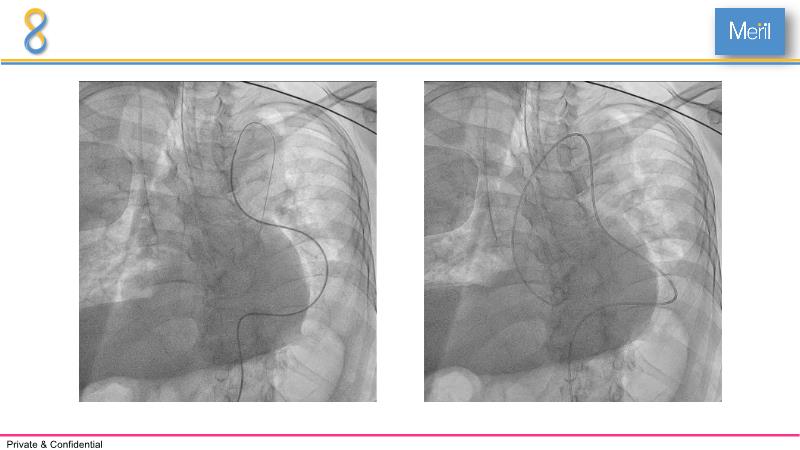

Through the presentation of several compelling cases, including an 88-year-old male with CKD, RBBB, moderate LV dysfunction, and severe aortic stenosis, a Type 1a bicuspid native AS, and an extraordinary TAVI in an 83-year-old with acute heart failure and comorbidities, this session will dive into the Myval Octapro THV. Learn about its key features, procedural impact, and potential clinical benefits. Discover the Octalign technique for predictable and precise commissural and coronary alignment, preserving coronary access. Gain insights into precise sizing, positioning, and deployment of the Myval THV series in real-world scenarios, and explore the relevance of pivotal Landmark RCTs in clinical practice.

- To understand the technique of precise sizing, positioning and deployment of Myval THV series in real world clinical scenarios